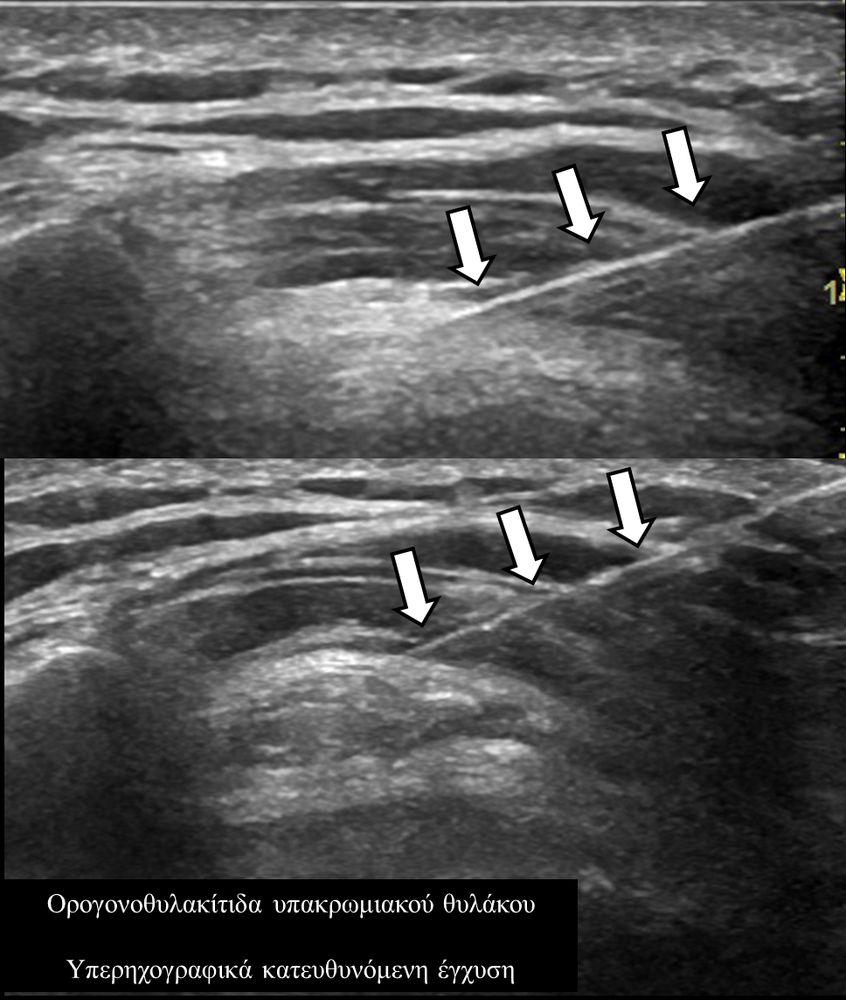

Υπό συνεχή υπερηχογραφική παρακολούθηση είναι δυνατόν να πραγματοποιηθούν κατευθυνόμενες εγχύσεις σε ορθοπαιδικές και ρευματολογικές παθήσεις. Αρχικά εντοπίζεται η παθολογική περιοχή και στη συνέχεια εξετάζεται η βέλτιστη οδός προσπέλασης. Ακολούθως γίνεται υπό άμεση και συνεχή υπερηχογραφική παρακολούθηση οι απαραίτητοι χειρισμοί και έγχυση φαρμάκων ακριβώς στη θέση της βλάβης.

Εχει αποδειχθεί ότι με την υπερηχογραφική καθοδήγηση εξασφαλίζεται:

- μεγαλύτερη ακρίβεια και αποτελεσματικότητα (αφού η έγχυση/θεραπεία γίνεται ακριβώς στηνπαθολογική περιοχή)

- καλύτερη ανοχή από τον ασθενή (λιγότεροι τραυματικοί χειρισμοί αφού έχουμε άμεση και συνεχή εποπτεία της βελόνας)

- μεγαλύτερη ασφάλεια (αποφυγή τρώσης νεύρων, αγγείων, γειτονικών ανατομικών δομών).

- σε ορογόνους θύλακες (πχ ώμου, αχιλλείου τένοντα, μείζονος τροχαντήρα κλπ)